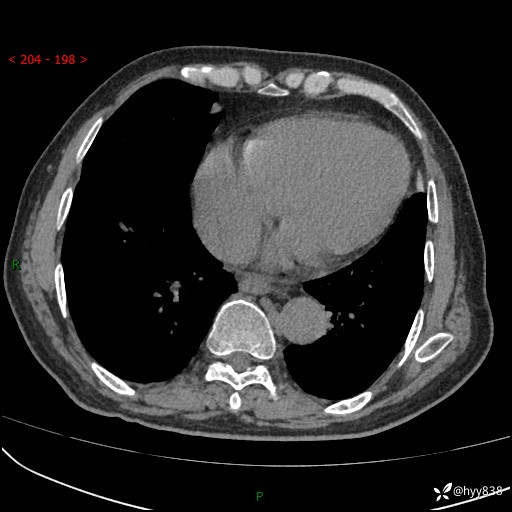

主诉:检查发现心脏肿物1周余。

现病史:患者一周余前因腹胀就诊我院消化科门诊,查心脏彩超提示右房内异常回声(粘液瘤?),无明显心慌、气喘、胸闷,无明显胸痛、咳嗽咳痰等不适,活动量增加后出现心慌、气喘不适。现为求进一步治疗,就诊我科,门诊遂以“心脏肿物”收入院。 自发病以来,精神睡眠一般,食欲尚可,大小便正常,体力下降,体重无明显变化。

胸部CT平扫+增强